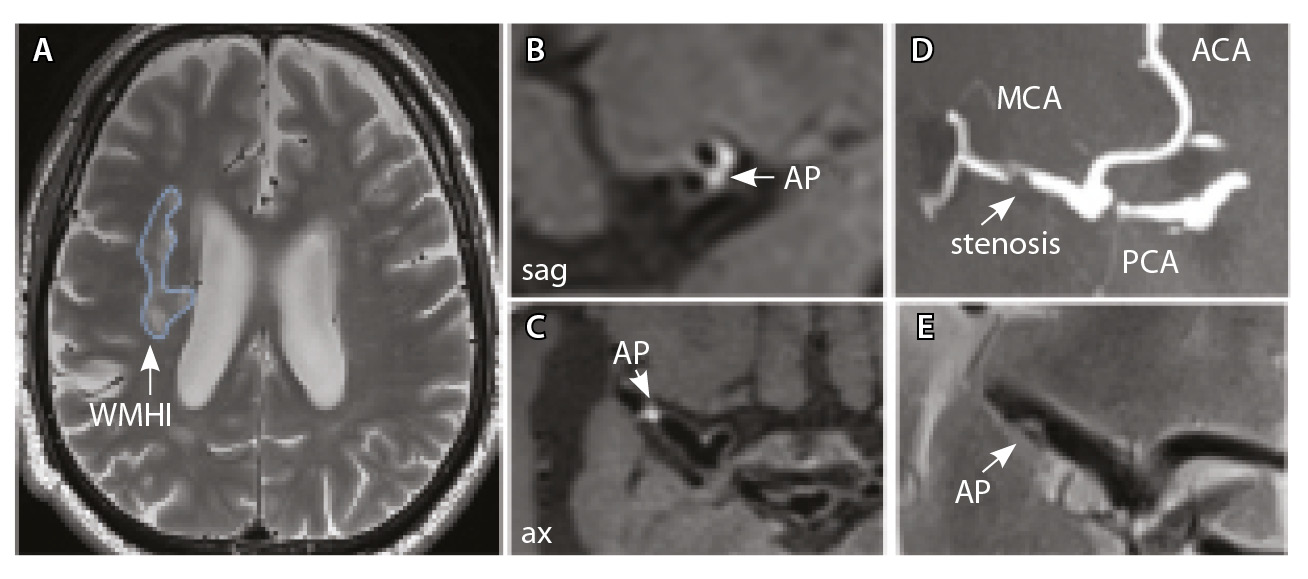

У всех включенных в исследование пациентов определялись атеросклеротические изменения брахиоцефальных артерий, в том числе на интракраниальном уровне, разной степени выраженности. У 9 больных отмечались признаки отрицательного ремоделирования артерий – выявление АСБ в стенке артерий, без сужения их просвета. Присутствовали изменения вещества головного мозга: инфаркты, в том числе лакунарные, – в 17 (58%) наблюдениях; МРТ-признаки церебральной микроангиопатии (ЦМА) – у 20 (68%) пациентов, среди них со степенью выраженности (F) по шкале Fazekas: F1 – у 7 (35%), F2 – у 4 (20%) (рис. 3), F3 – у 9 (45%) (рис. 4) [27]. Средние, большие и обширные инфаркты мозга зарегистрированы у 6 (20%) больных. Для количественной оценки изменений АСБ выбирался наиболее пораженный участок артерий (за исключением окклюзии): в 12 (41,4%) случаях это был интракраниальный сегмент внутренней сонной артерии (ВСА), в 10 (34,5%) – средней мозговой артерии (СМА), в 6 (20,7%) – базилярной артерии (БА), в 1 (3,4%) – задней мозговой артерии (ЗМА) (см. табл. 1).

Рис. 4. Пациент К., 69 лет, с признаками церебральной микроангиопатии (F2 по шкале Fazekas) и атеросклерозом интракраниальных артерий, с формированием гемодинамически значимого стеноза в сегменте М1 правой средней мозговой артерии (СМА): А – магнитно-резонансная томография (МРТ), режим Т2-взвешенного изображения: видны множественные сливные очаги гиперинтенсивности белого вещества (ГИБВ); Б, В – МРТ сосудистой стенки, режим T1-TSE-db-FS после контрастного усиления: в сегменте М1 правой СМА визуализируется эксцентричная атеросклеротическая бляшка (АСБ), интенсивно накапливающая контрастный препарат; Г – трехмерная магнитно-резонансная времяпролетная (3D ToF) ангиография: виден стеноз правой СМА в сегменте М1; Д – режим HR Т2-TSE: видна АСБ в сегменте М1 правой СМА; ax – аксиальная, sag – сагиттальная плоскости; ЗМА – задняя мозговая артерия; ПМА – передняя мозговая артерия